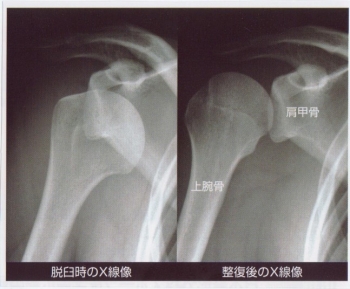

肩関節脱臼は、脱臼の中でもっとも頻度が多く、脱臼の50%以上が肩です。

前方・後方・下方・上方脱臼がありますが、ほとんど前方脱臼です。

肩関節が約30°外転し、上腕骨が外転内旋している

三角筋部の膨隆が消失し、肩峰が角上に突出する

肩峰の下が空虚となり、烏口突起の下に骨頭が触知できる